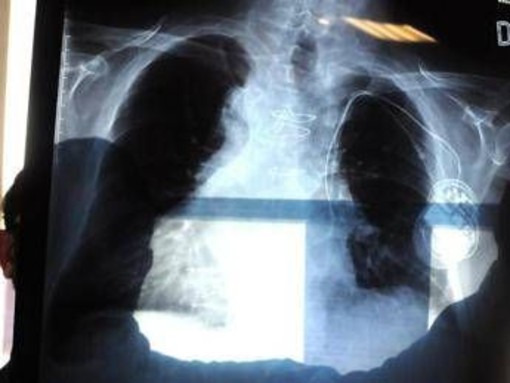

Polmonite, ogni anno in Italia 150mila ricoveri e 9mila morti: i sintomi

(Adnkronos) - Una diagnosi di polmonite è fonte di preoccupazione a qualsiasi età. Questa malattia, infatti, "è una causa di ricovero ospedaliero da sempre e, purtroppo, anche causa di morte. Tutti gli anni sono 150mila gli italiani ricoverati e 9mila i decessi. Ma attualmente non registriamo grandi cambiamenti nei numeri, l'epidemiologia è stabile. E come sempre, ogni anno, si registrano complicanze serie che riguardano soprattutto le persone a rischio: gli anziani, i bambini, i pazienti cronici". A fare il quadro per l'Adnkronos Salute è Claudio Micheletto, presidente dell'Associazione nazionale pneumologi ospedalieri (Aipo), in un periodo in cui alcuni casi noti hanno riportato all'attenzione questa patologia, in particolare per la forma interstiziale, come per la morte del maestro Peppe Vessicchio o per il ricovero dell'allenatore del Bologna Vincenzo Italiano.